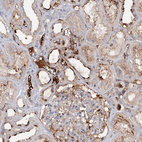

Immunohistochemical staining of human spleen shows strong membranous positivity in cells in red pulp.